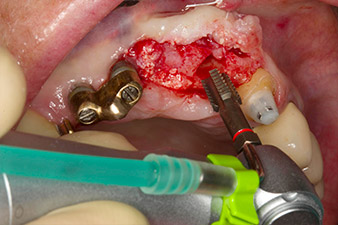

pilot drilling is performed with the new Implantmed and the WS-56 L contra-angle handpiece

Fig. 2: Two months later the pilot drilling is performed with the new Implantmed and the WS-56 L contra-angle handpiece (programme P1, ratio 1:1). The cooling is performed via the spray tube positioned on the left (for right-handed users).